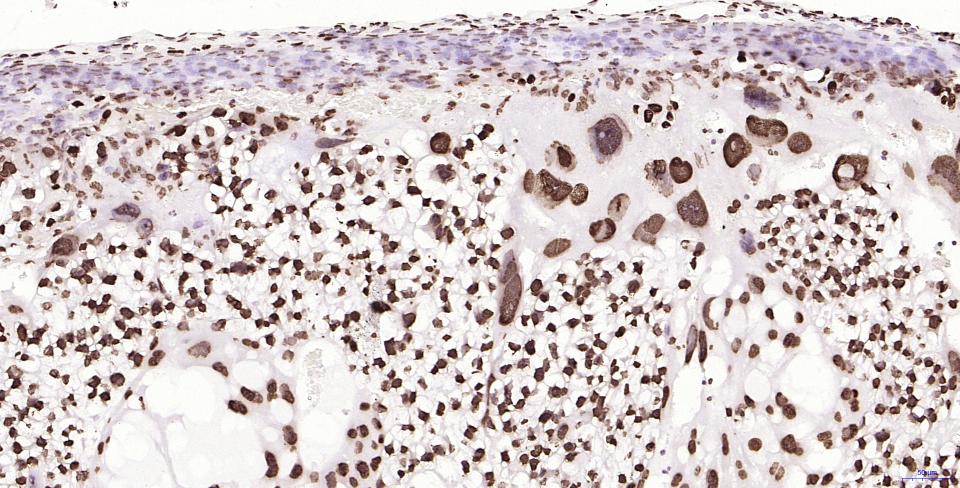

Paraformaldehyde-fixed, paraffin embedded Human Breast Cancer; Antigen retrieval by boiling in sodium citrate buffer (pH6.0) for 15 min; Antibody incubation with Histone H2A.X Monoclonal Antibody, Unconjugated(bsm-61080R) at 1:200 overnight at 4°C, followed by conjugation to the SP Kit(Rabbit, SP-0023) and DAB (C-0010) staining.

Paraformaldehyde-fixed, paraffin embedded Human Colon Cancer; Antigen retrieval by boiling in sodium citrate buffer (pH6.0) for 15 min; Antibody incubation with Histone H2A.X Monoclonal Antibody, Unconjugated(bsm-61080R) at 1:200 overnight at 4°C, followed by conjugation to the SP Kit(Rabbit, SP-0023) and DAB (C-0010) staining.